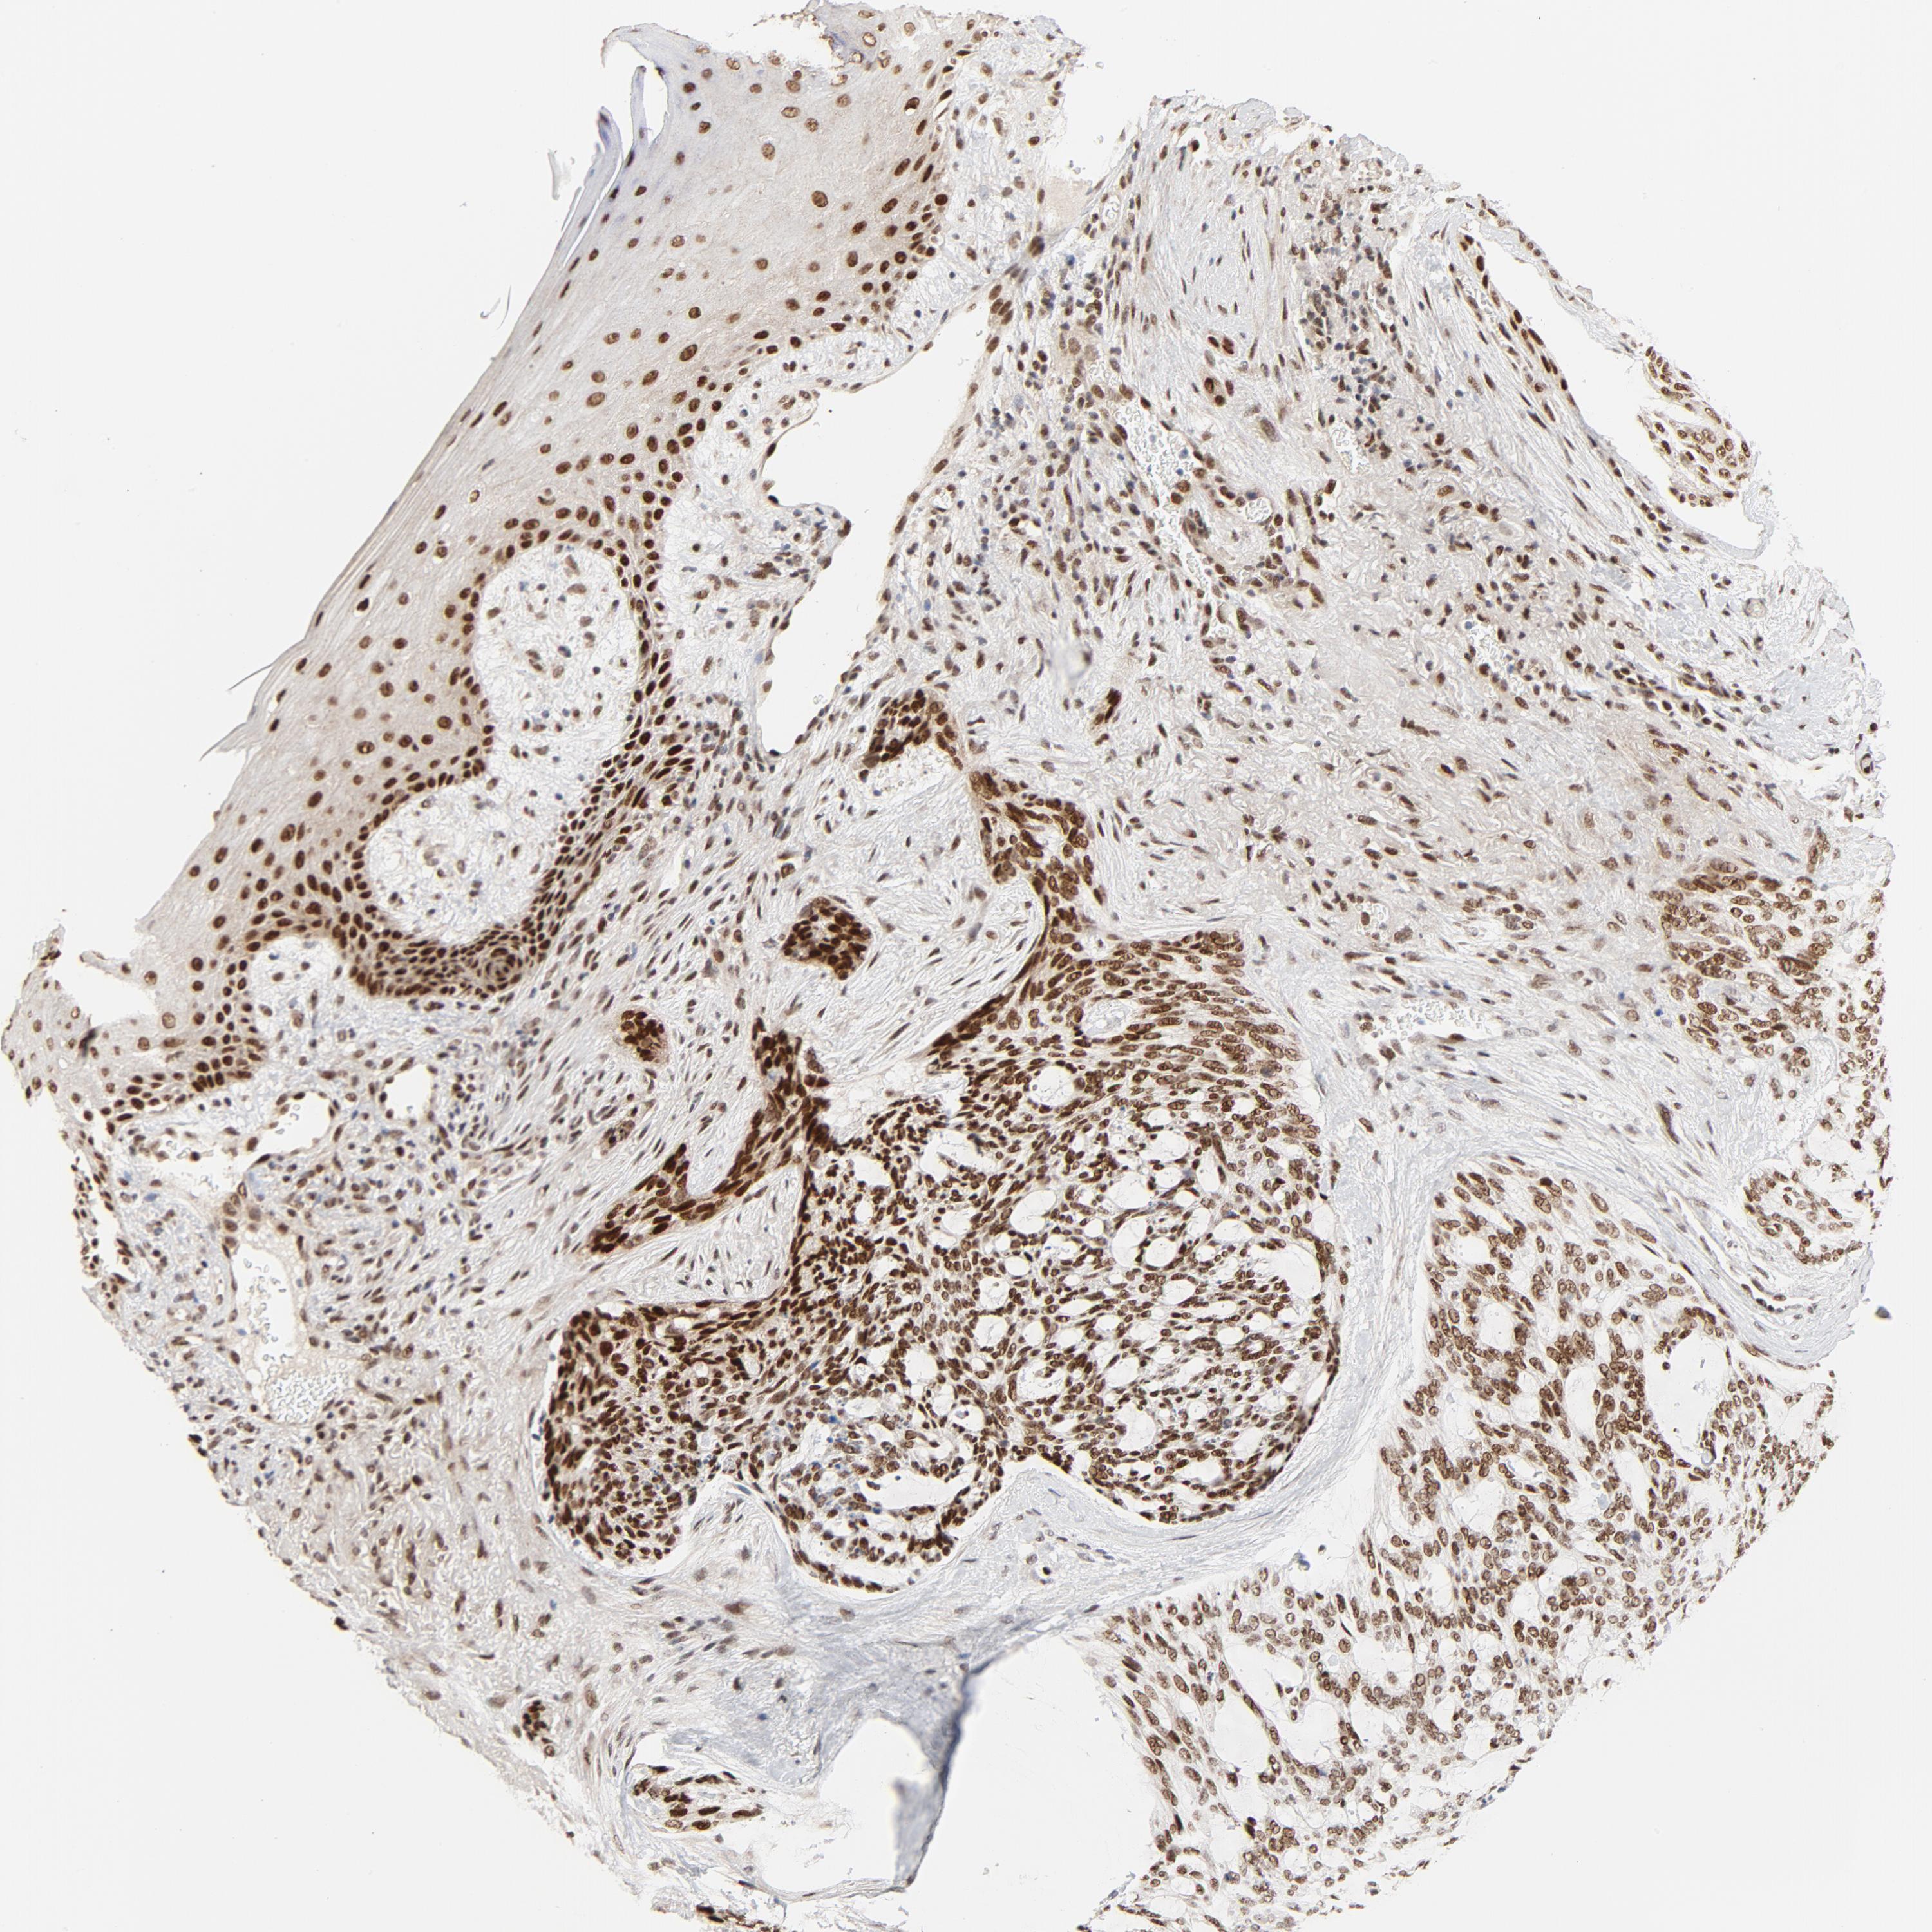

SKIN CANCER - Protein expressioni

A mouse-over function shows sample information and annotation data. Click on an image to view it in a full screen mode. Samples can be filtered based on level of antibody staining by selecting one or several of the following categories: high, medium, low and not detected. The assay and annotation is described here.

Antibody stainingi

Antibody staining in the annotated cell types in the current human tissue is reported as not detected, low, medium, or high, based on conventional immunohistochemistry profiling in selected tissues. This score is based on the combination of the staining intensity and fraction of stained cells.

Each image is clickable and will lead to virtual microscopy that enables deeper exploration of all samples and also displays staining intensity scores, fraction scores and subcellular localization as well as patient and tissue information for each sample.

Antibody HPA026638

Basal cell carcinoma